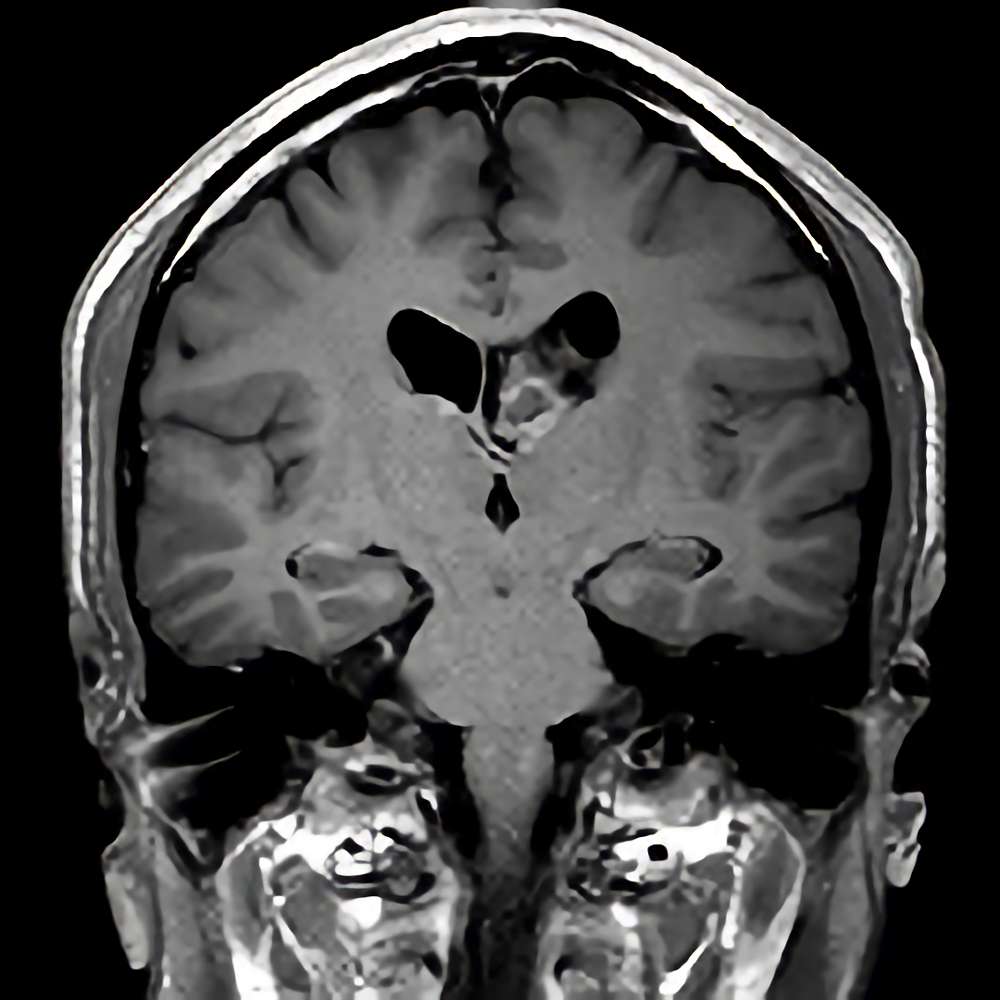

No.’21_27 手術前1

No.’21_27 手術前2